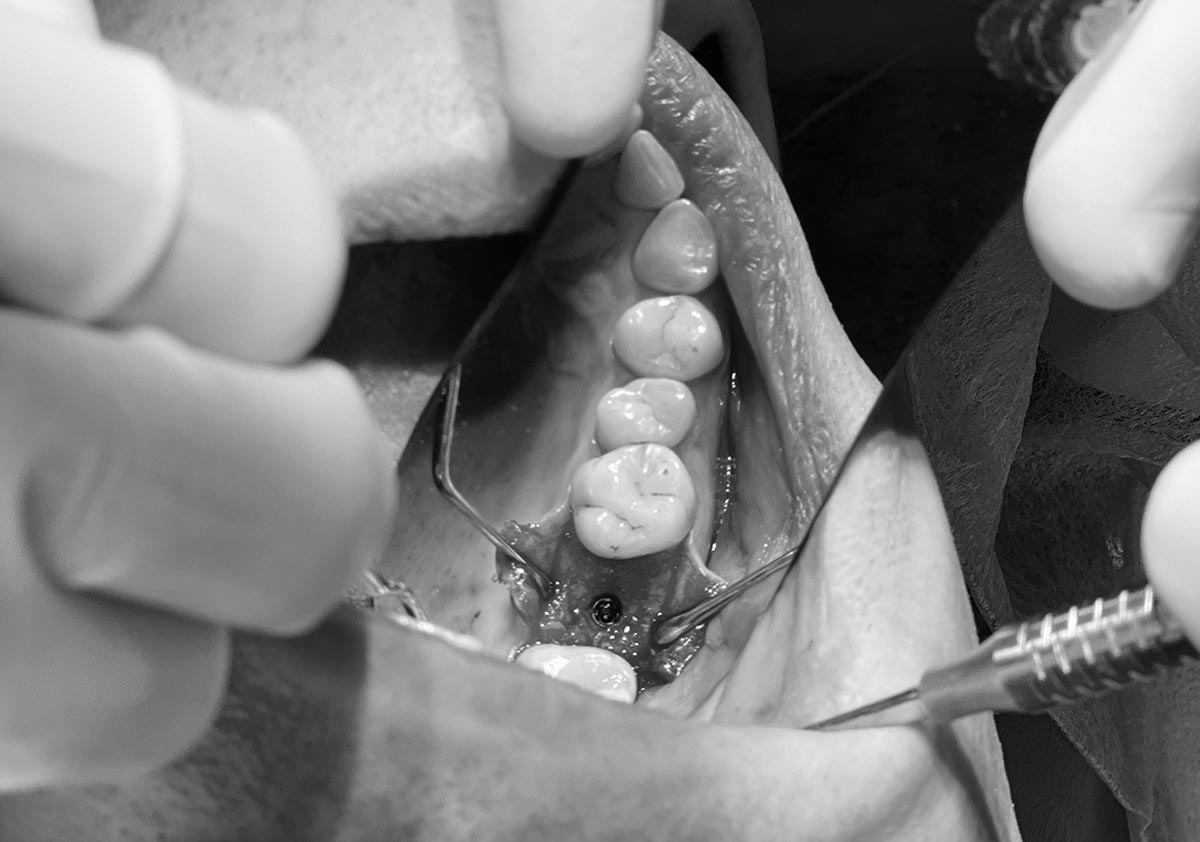

В день процедуры стоматолог производит местную анестезию для устранения боли, после чего удаляет избыточные ткани десен. Коррекция десен может производиться лазером или хирургическими инструментами в зависимости от показаний.

Лоскутная пластика десен является процедурой для восстановления или увеличения объема мягких тканей десен, проводимой путем переноса ткани из другого участка полости рта или с использованием донорских или синтетических материалов. Процедура помогает восстановить эстетику улыбки, улучшить защиту зубов и способствует здоровью десен. Она предусматривает тщательную подготовку, точную переноску ткани и послеоперационный уход для обеспечения успешной приживки и достижения желаемых результатов.